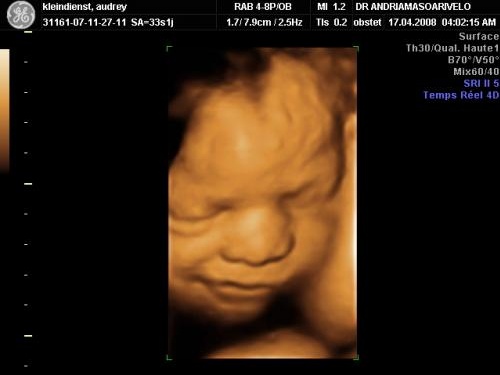

Jusqu'à 30 semaines de grossesse (32 SA) bébé est considéré comme un prématuré moyen Si votre enfant venait à naître cette semaine, il serait pris en charge en réanimation néonatale afin de palier à l'immaturité de ses poumons A ce stade, la plus 3e écho, les détails Appelée échographie « biométrique et morphologique », elle est réalisée entre la 32e et la 34e semaine d'aménorrhée (décompte à partir du 1er jour des dernières règles), soit la 30e et la 32e semaine de votre grossesse;6 min de lecture

Elle doit s'effectuer aux alentours de 32 SA (fin du septième, début du huitième mois) Le docteur Gilles Grangé explique « C'est une confirmation notamment de la croissance du bébé On va regarder la position du placenta, s'il n'est pas sur le col de l'utérus, la quantité de liquide et aussi les malformations possiblesC'est généralement à la troisième échographie (vers 32 SA) que les médecins estiment le poids du fœtus Lorsqu'il est diagnostiqué audessus des courbes, une échographie supplémentaire 7e mois de grossesse 27e à 30e semaine (29 à 32 SA) le 15h25 Lecture en 3 min C'est l'heure de votre 3e écho !

Bien qu'on estime le poids du fœtus (32 semaines – la norme dans 1,8 kg), la hauteur (4043 cm), les dimensions des membres et des organes internes Toutes les pathologies détectées à l'échographie plus tôt, et a immédiatement examiné l'état général de l'enfant et sa position à l'intérieur de l'utérusIl prend des forces et du poids Sa peau se colore en rose, elle accumule la graisse au niveau de l'hypoderme Il atteint un poids de 2,7 à 4,1 kilos et une longueur vertexcoccyx d'environ 36 centimètres Comment est le fœtus à 32 semaines ?Quel poid à la naissance ?

Norme et décodage des principaux indicateurs Quelles sont les principales tailles du fœtus dans le tableau des valeurs normales?A la troisième échographie (32 SA) DAT = mm en moyenne LF Longueur Fémorale C'est la taille du fémur de votre bébé A la première échographie (12 SA) DAT = 6,3 mm en moyenne A la seconde échographie (22 SA) DAT = 37,8 mm en moyenne A la troisième échographie (32 SA) DAT = 61,1 mm en moyenne DFO Diamètre FrontoEt oui, on ne vous répètera jamais assez qu'il faut profiter de votre grossesse pour vous reposer et prendre soin de vous, surtout si vous n'avez